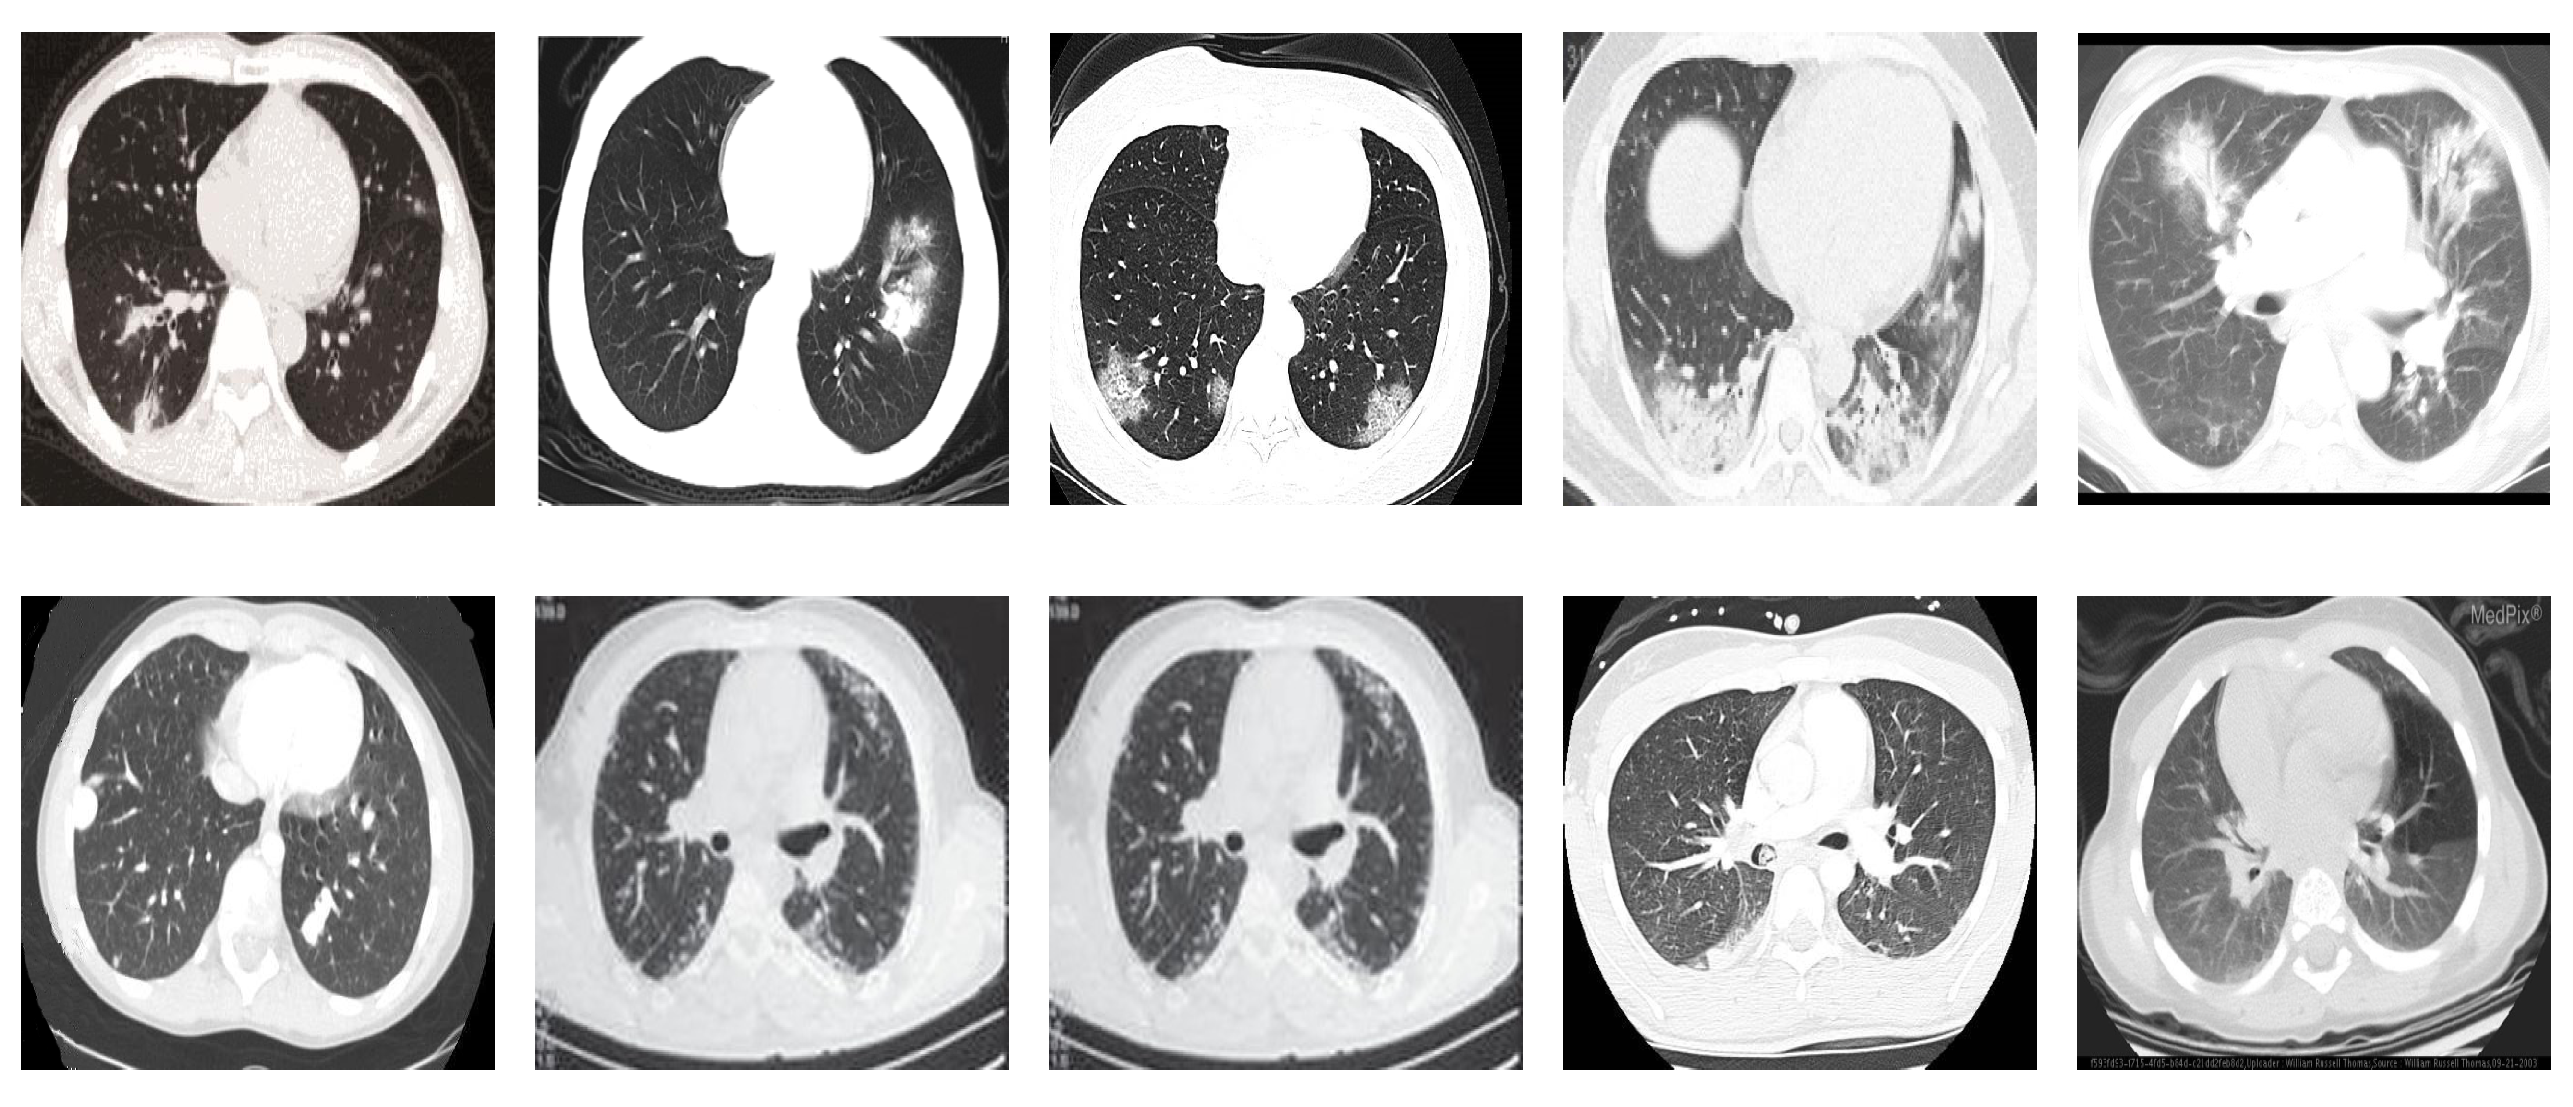

SARS-CoV-2 CT Scan dataset [53]: The dataset was collected from hospitals of Sao Paulo, Brazil, with a total of 2482 CT scans acquired from 120 patients of both genders. It is composed of 1252 scans for patients infected with SARS-CoV-2, and 1230 scans for patients infected with other lung diseases. The CT scans have varying spatial sizes between and , and are available in PNG format. CT scans from this dataset are shown in Figure 7.

Figure 7.

Examples of chest CT scans from the SARS-CoV-2 CT dataset. The first row represents CT scans diagnosed with COVID-19, whereas the second row represents non-COVID-19.